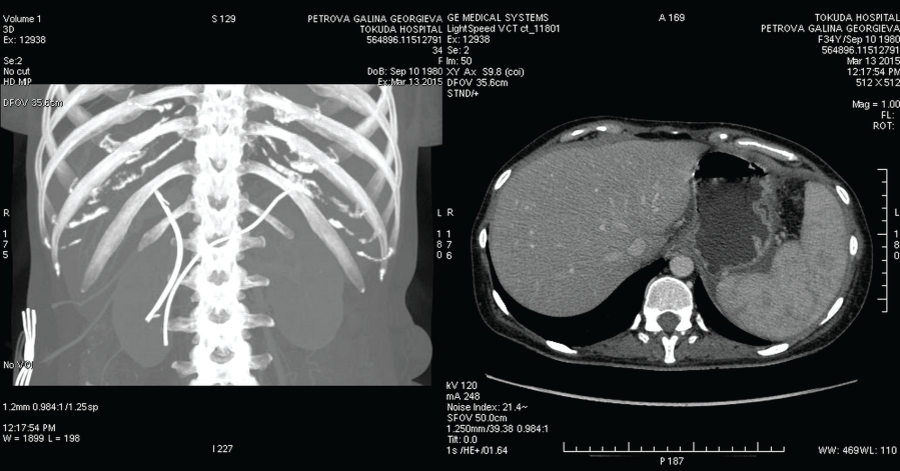

Ten days later she was admitted again with massive fresh bleeding from the contact drainage-500 ml for the last 12 hours. The laboratory tests showed a normocytic normochromic anemia (hemoglobin 9.6 mg/dl, hematocrit 30.0%) and normal coagulation status. Conservative therapy including proton pomp inhibitors (Esomeprasole -80 mg intravenous bolus followed by an 8 mg/h continuous infusion), fresh frozen plasma infusion, Terlipressin (intravenous bolus injection 2 mg/4 h followed by a continuous infusion 2 mg/24 h), vitamin K and Dicynone infusions were administered. However, intermittent bloody secretion from the contact drainage (150-900 ml/24 h) and transcystic biliary secretion (500 ml/24 h) persisted. The abdominal CT showed persistent pancreatic pseudocysts with peripancreatic fluid collections, a dilated pancreatic duct, splenic vein thrombosis and ascites (Figure 1). CT angiography depicteda homogeneously contrasted abdominal aorta without aneurysms or dissection, normal separation and distribution of its visceral branches and homogeneously contrasted lumens without contrast leakage.